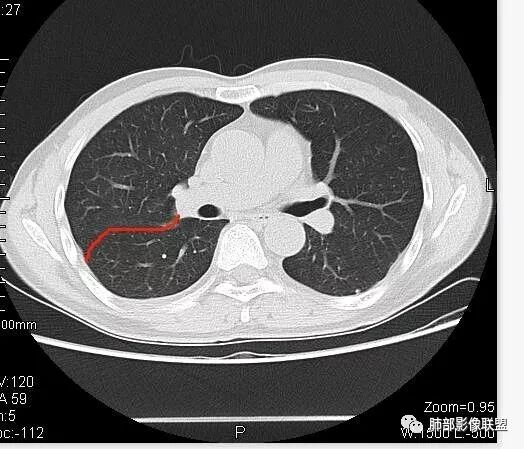

但是现在的片显示,其主体在下叶,中叶支气管壁由下朝上有推移

南边:就不符合这个原理

初学者:如果中叶病灶,叶间裂应该下推,也不会上推

而且支气管內密度较高是粘液栓,远端支气管也是通畅,所以支气管内是因为受压所以痰液引流不畅。

南边:从叶裂的变形,下朝上,越来越朝前扭曲,提示叶裂局部有朝前上推移的趋势

南边:下叶的支气管受压后移、变形